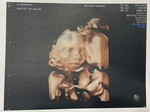

ใครมีประสบการณ์แบบบ้านนี้ไหมคะ ท้องแรกน้องโครโมโซมคู่ 21 เกิน ยุติการตั้งครรภ์ไปตอน เดือนมีนาคม 2565 ท้องสองไข่ตกตอนต้นเดือนธันวาคมไปซาวด์สองครั้ง สรุปน้องเป็นท้องลม รู้สึกหดหู่ เสียใจมากค่ะ หมอให้รอ 2 อาทิตย์ให้น้องหลุดเอง แต่ถ้าไม่หลุดให้ไปโรงบาลเพื่อทำการเหน็บยาค่ะ

บ้านนี้ก็เป็นค่ะ 11วีคเจอแต่ถุงตั้งครรภ์ แล้วมีเลือดออกด้วย คุณหมอบอกว่าน่าจะเป้นท้องลม

ของเราก็ไม่เจอค่ะ เจอแต่ถุงไข่แดง😭

ซาวด์ตอนเช้าทั้งสองทางเลยค่ะ ไม่เจอน้องเลยค่ะ ก่อนหน้านี้ 2 อาทิตย์ก็ไม่เจอค่ะ